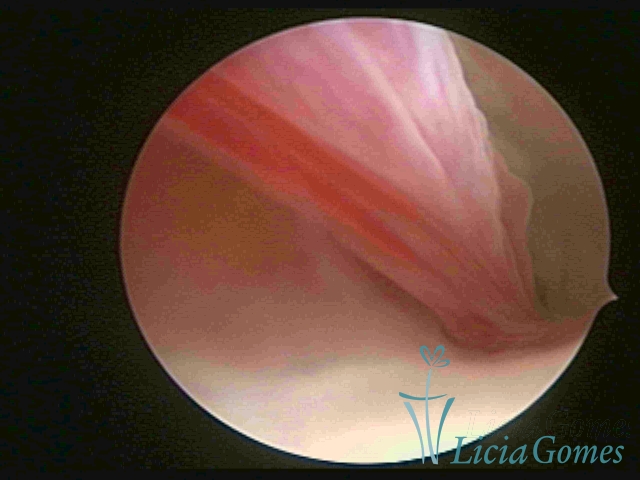

ENDOCERVICAL POLYPS

Benign tumors resulting from the reactive focal proliferation to inflammatory processes or hyperestrogenism situations, which may be sessile (with a large implantation) or stalked.